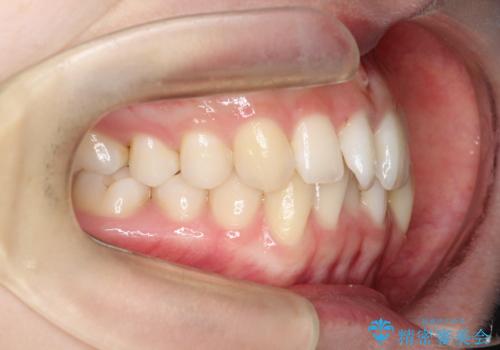

前歯のガタガタと欠損部を改善

- 患者様は、前歯のガタガタ(叢生)と左下5番の欠損部が気になるとのことで来院されました。診断の結果、インビザラインを用いて前歯の叢生を整えながら、左下5番の欠損部にはインプラント治療を計画しました。矯正治療により、歯並びを改善すると同時に、噛み合わせのバランスも向上させることを目標としました。矯正期間とインプラントの治療計画を並行して進めることで、患者様のご希望に応えるプランを立てました。

前歯の叢生改善のため、インビザラインによる透明で目立たない矯正装置を使用しました。治療中は、歯の移動による負担を最小限に抑えつつ、歯列全体のバランスを考慮して進めました。左下5番の欠損部には、矯正終了後にインプラントを埋入し、自然で機能的な咬合を回復しました。治療期間中、患者様には装置の正しい装着と日々の清掃を徹底していただき、歯肉やインプラント周囲の健康を保つようサポートしました。結果として、美しい歯並びと快適な噛み合わせを両立させることができました。